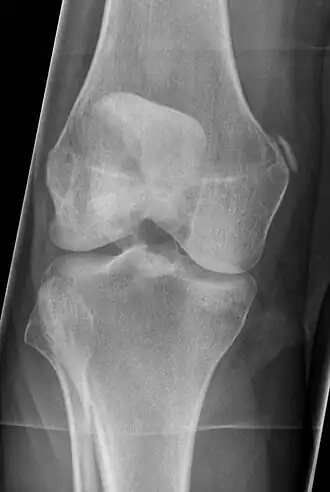

Het syndroom van Pellegrini-Stieda is een vrij zeldzame aandoening van de knie, waarbij er pijn en wat zwelling optreedt aan de condylus medialis femoris, dit is de knobbel onderaan het dijbeen, soms met, soms ook zonder duidelijk voorafgaand letsel. Op de röntgenfoto is een kalksikkeltje te zien ter hoogte van de aanhechting van de mediale knieband, het ligamentum collaterale mediale van de knie, en soms verkalkt het ligament geheel. De pijnklachten gaan meestal na enige maanden over. De behandeling bestaat uit het voorkomen van bewegingsbeperking door oefenen en waar nodig pijnstilling. Bij pijn op deze plaats kan ook gedacht worden aan een gewoon letsel van de knieband of aan aseptische botnecrose.